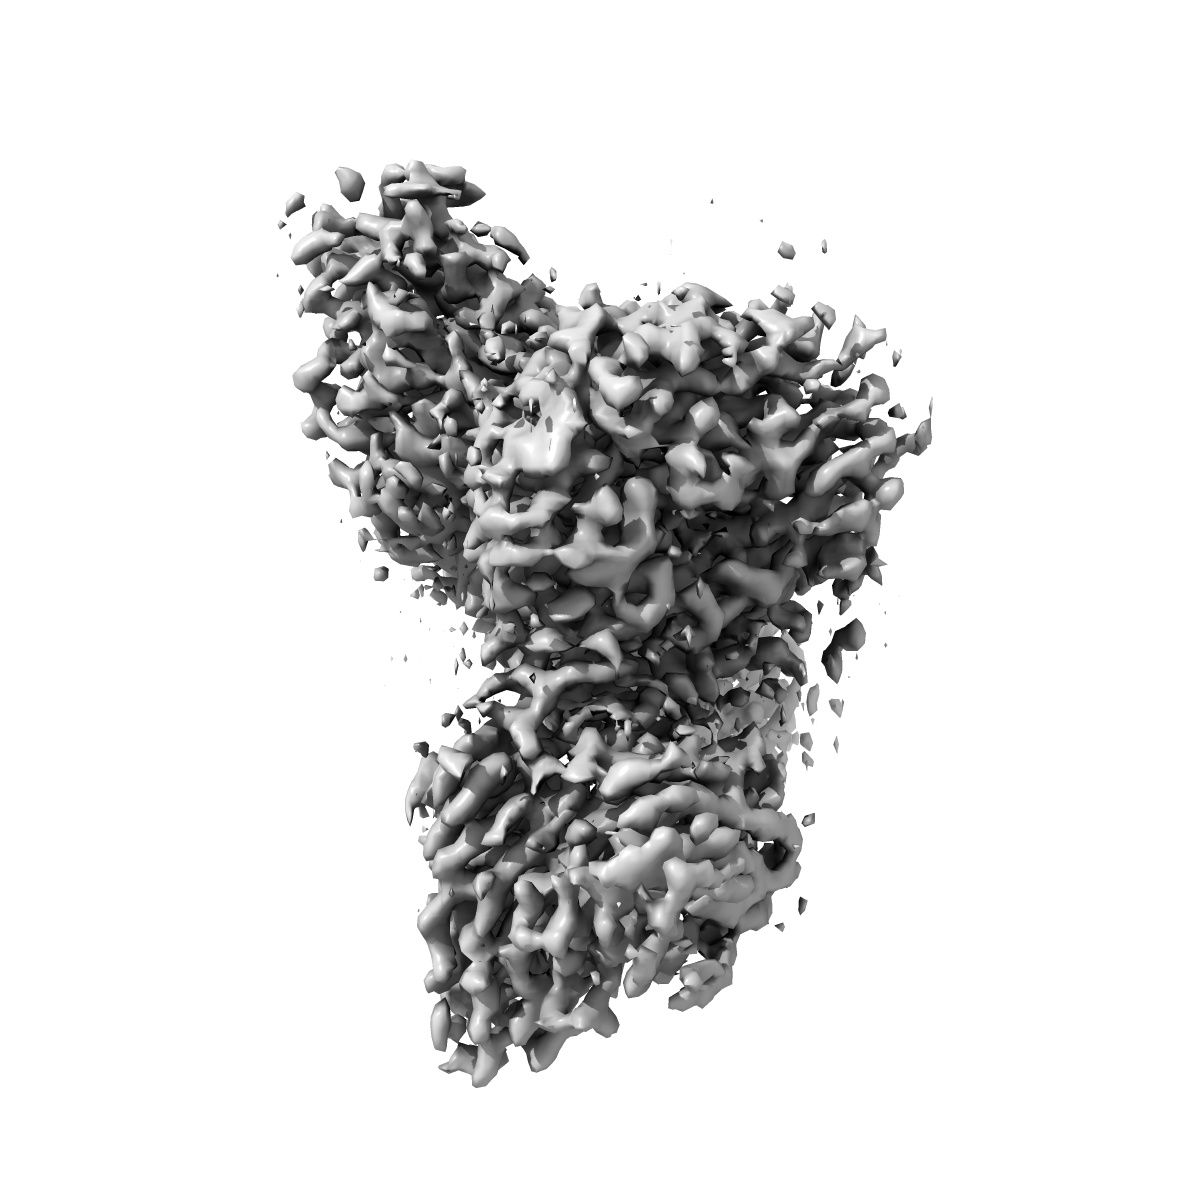

Cryo-EM structure of human galanin receptor 2

Single-particle3.11 Å

Sample: Human galanin receptor 2 complex with Gq heterotrimer

Structure of the human galanin receptor 2 bound to galanin and Gq reveals the basis of ligand specificity and how binding affects the G-protein interface.